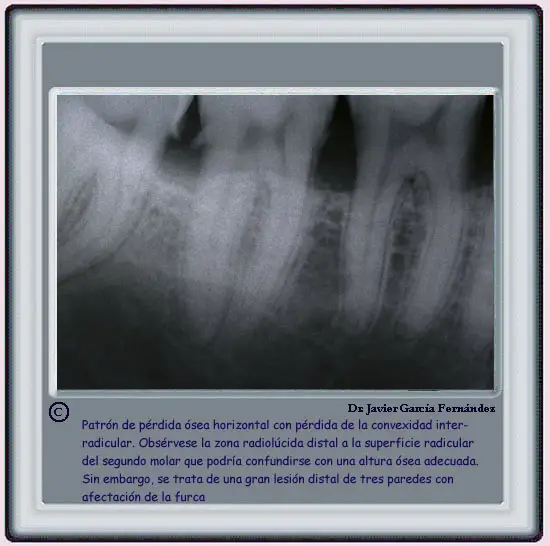

image218